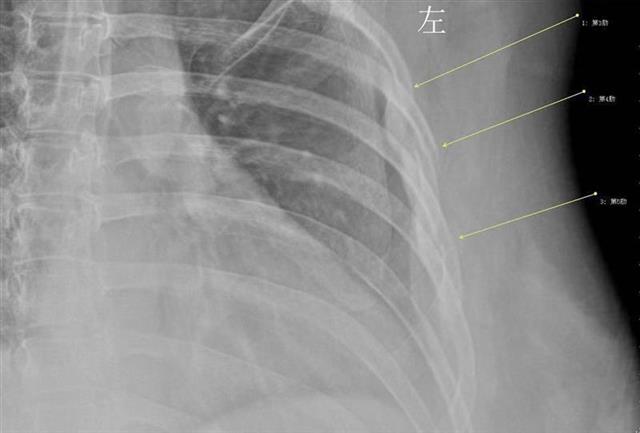

次の日に原因を知るために病院に行きX線検査したところ、彼女の診断結果は咳のせいで3、4、5番目の肋骨が骨折していたことが判明。